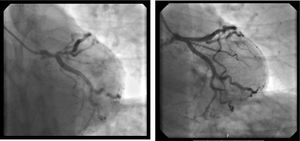

A coronariografia revelou doença importante na artéria descendente anterior – estenose ostial de 85% e estenose proximal de 70% até à emergência da primeira diagonal, não tendo os restantes vasos lesões angiograficamente significativas. Foi realizada pré‐dilatação com balão da lesão proximal e ostial da descendente anterior e implantado seguidamente um stent com antiproliferativo 3,5 x 28mm com bom resultado angiográfico final (figura 3).